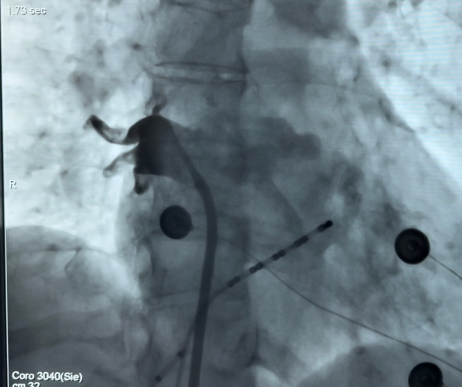

(术中放电即刻高尖肺静脉电位脱落)